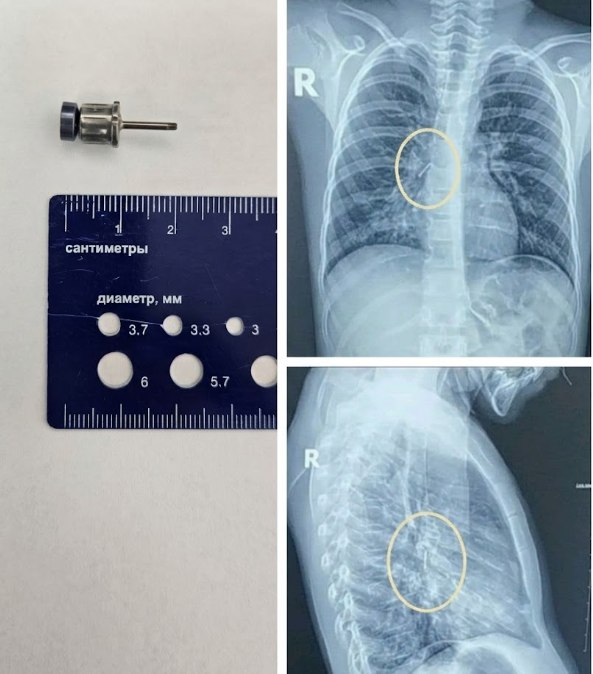

Стоматологічна викрутка: Навіть під час медичних маніпуляцій може статися непередбачуване. Інструмент для імплантації випадково потрапив у дихальні шляхи пацієнта. Лікарі нашого центру успішно впоралися з цим складним завданням.